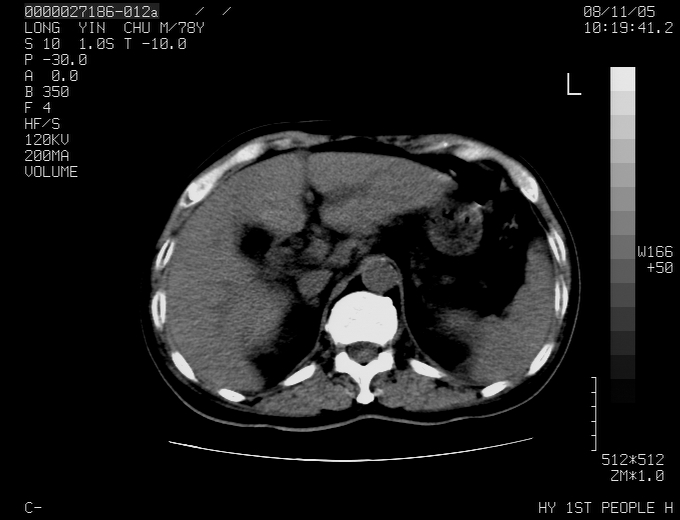

标题: CT16532:M78Y,肝脏病变,请会诊

腹胀,腹痛就诊,男性,78岁,外院b超未见异常。

肝ca,脾肾转移

考虑弥漫性肝癌并脾及双肾转移.双侧胸水.

肝脾肾转移瘤可能性大,左肾不除外梗塞,双侧胸水

考虑弥漫性肝癌并脾及双肾转移,双侧胸水。